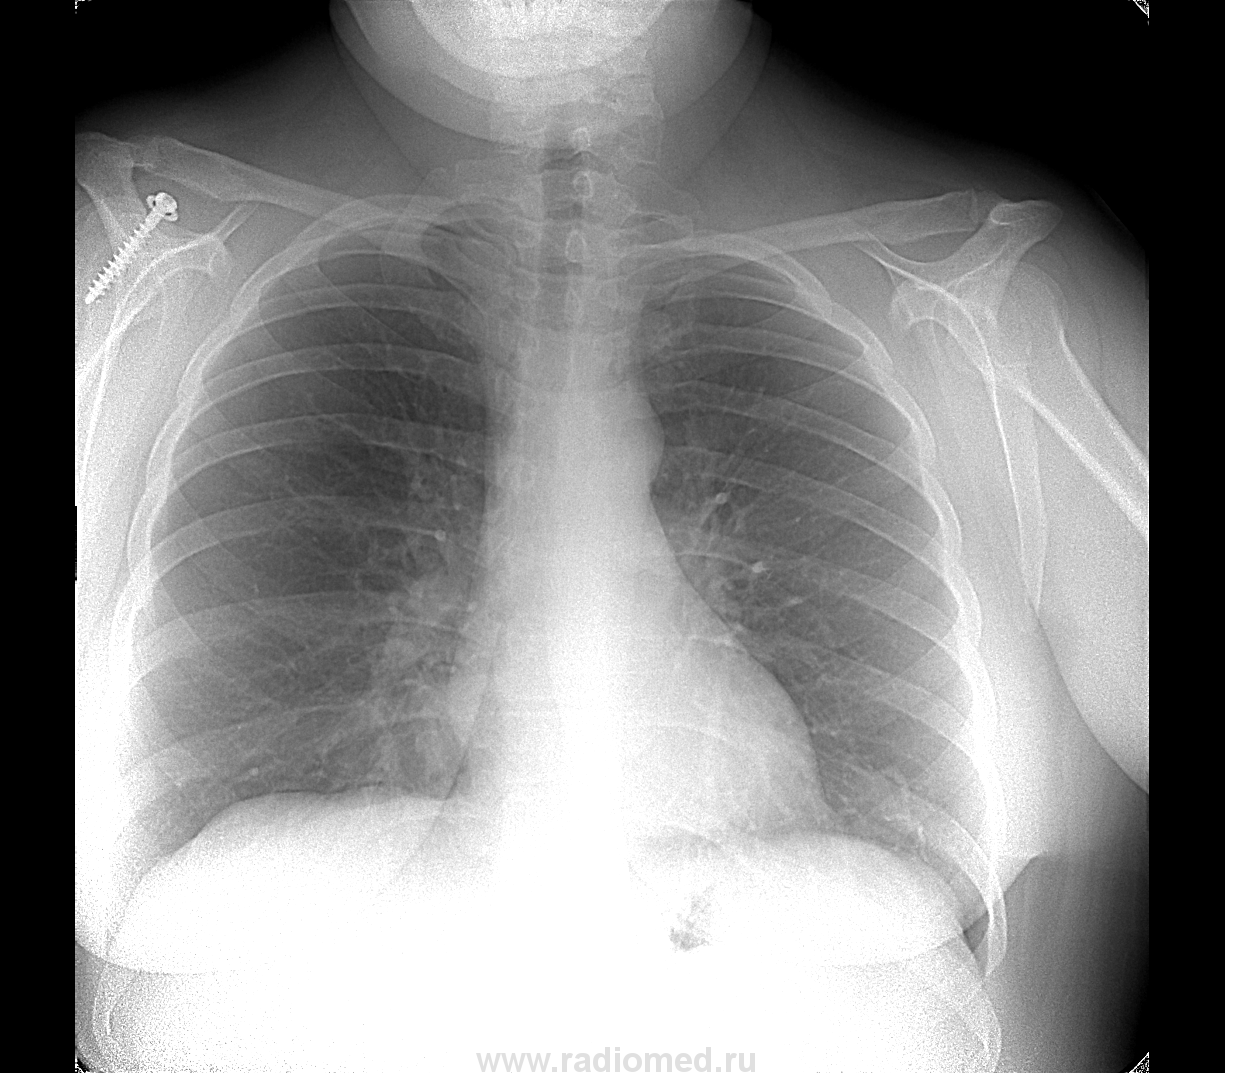

Дама, 1966 года рождения. Жалоб нет.

первый снимок в 01.2010г.

Не буду мучать, что скажете по скиалогии.

Итак, имеем: нечто периферическое полостное (то, чего раньше не было) с лимфоаденопатией корня и средостения. На мой взгляд , наиболее вероятно  - р-признаки полостной формы периферического рака с метастазами в средостение.

Учитывая динамику гистологически вероятно будет мелкоклеточный рак.

Но верификация обязательна. Возможна другая патология